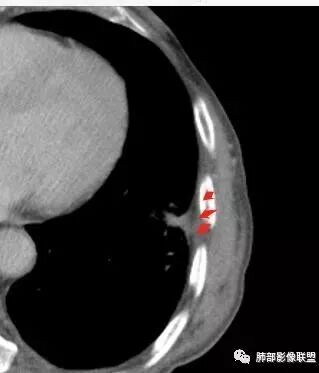

鳞癌,与吸烟关系密切,起源于支气管粘膜上皮,典型的征象就是支气管截断,周围型鳞癌往往体积较大,有时候与支气管关系不好判断,需要多平面重建看支气管的关系。

鳞癌因为侵袭性力较强,容易直接侵犯胸膜、胸壁,而周围型肺癌侵犯胸壁的90%癌肿是鳞癌,这也是鳞癌的一个特征性表现。邻近胸壁的脂肪层消失,胸壁肿块形成或有肋骨皮髓质边界不清的侵蚀破坏(而非边缘硬化或崩解)是瘤体向周围直接侵犯的可靠征象。

鳞癌因为破坏力强,其内可见灶样坏死区,坏死边界不清,其内血管破坏彻底。

肉瘤样癌也好发于中老年人,与吸烟关系密切。肿块体积往往较大,也是好发于胸膜下伴胸壁侵犯,也容易发生坏死,与周围型鳞癌的主要鉴别点在于支气管的关系和病灶内强化的情况。肉瘤样癌以环状强化为主,病灶周边多以癌组织为主,血供丰富,病灶中心区则以肉瘤成分为主,血供较差,易出现粘液样变性、坏死、出血,坏死边界清楚。